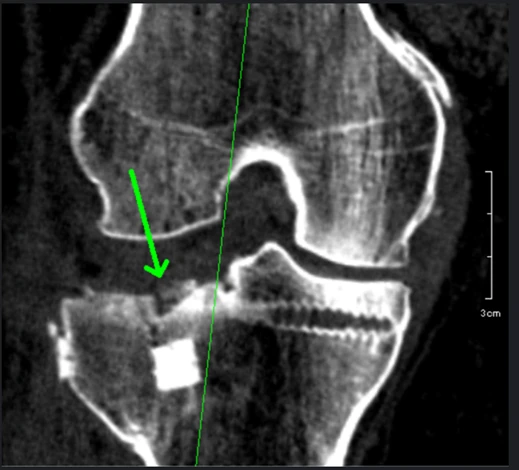

② 脛骨高原骨折のCT画像

※矢印部で段差が認められます。